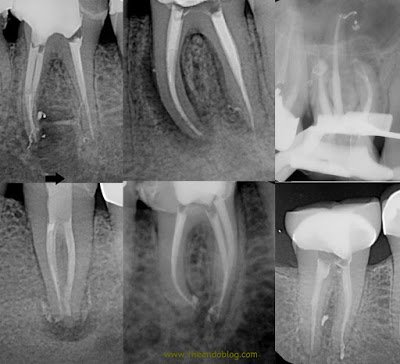

In our practice at Superstition Springs Endodontics, we have been using active irrigation for years, starting with ultrasonic and now currently using sonic activation on every case. We have found that with adequate irrigation time, sonic activation and removal of the smear layer (using EDTA), we are finding and filling more and more lateral canals, accessory canals, apical deltas. (The use of radiopaque sealers also increases the visibility) In my opinion, its difficult to say how much of this is attributed to the removal of the smear layer – but I expect that it is a combination of the active irrigation and removal of smear layer.

Here are a few of the cases demonstrating the benefits of active, sonic irrigation and smear layer removal.

So as you can see, the proper cleaning, shaping, active irrigation and removal of smear layer of the canals allows for us to open the lateral, accessory and apical deltas that we know exist in the complex canal anatomy.

Whether this changes the outcomes or success rate of the endodontic procedure is unknown, but it sure looks pretty!